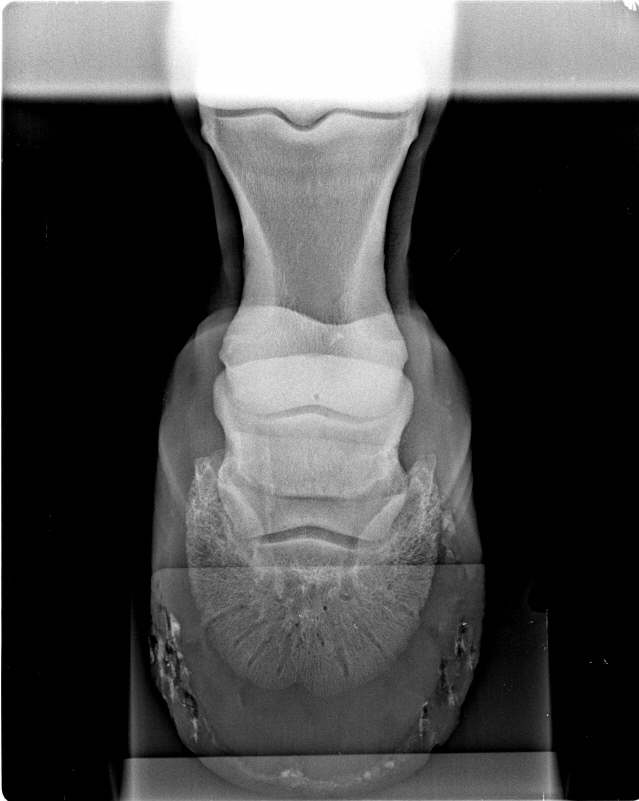

Röntgen Fall2

Oxspringaufnahme weitgehend unauffällig